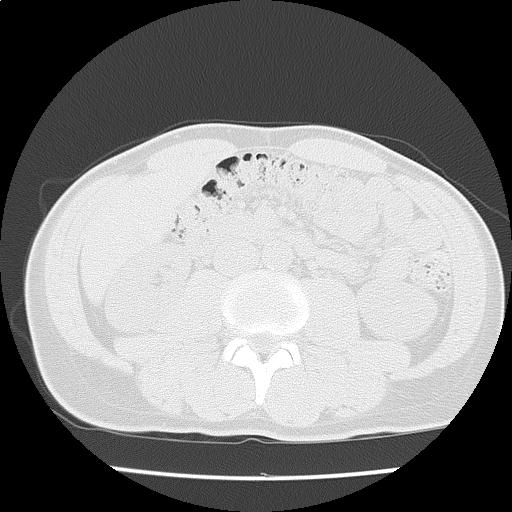

【読影指南】症例画像11

内視鏡で食道静脈瘤有り。甲状腺から骨盤までスクリーニング

年齢: 45歳

性別: 男性

検査部位: 胸腹部

検査種別: CT

CTスライス画像

CTスライス1